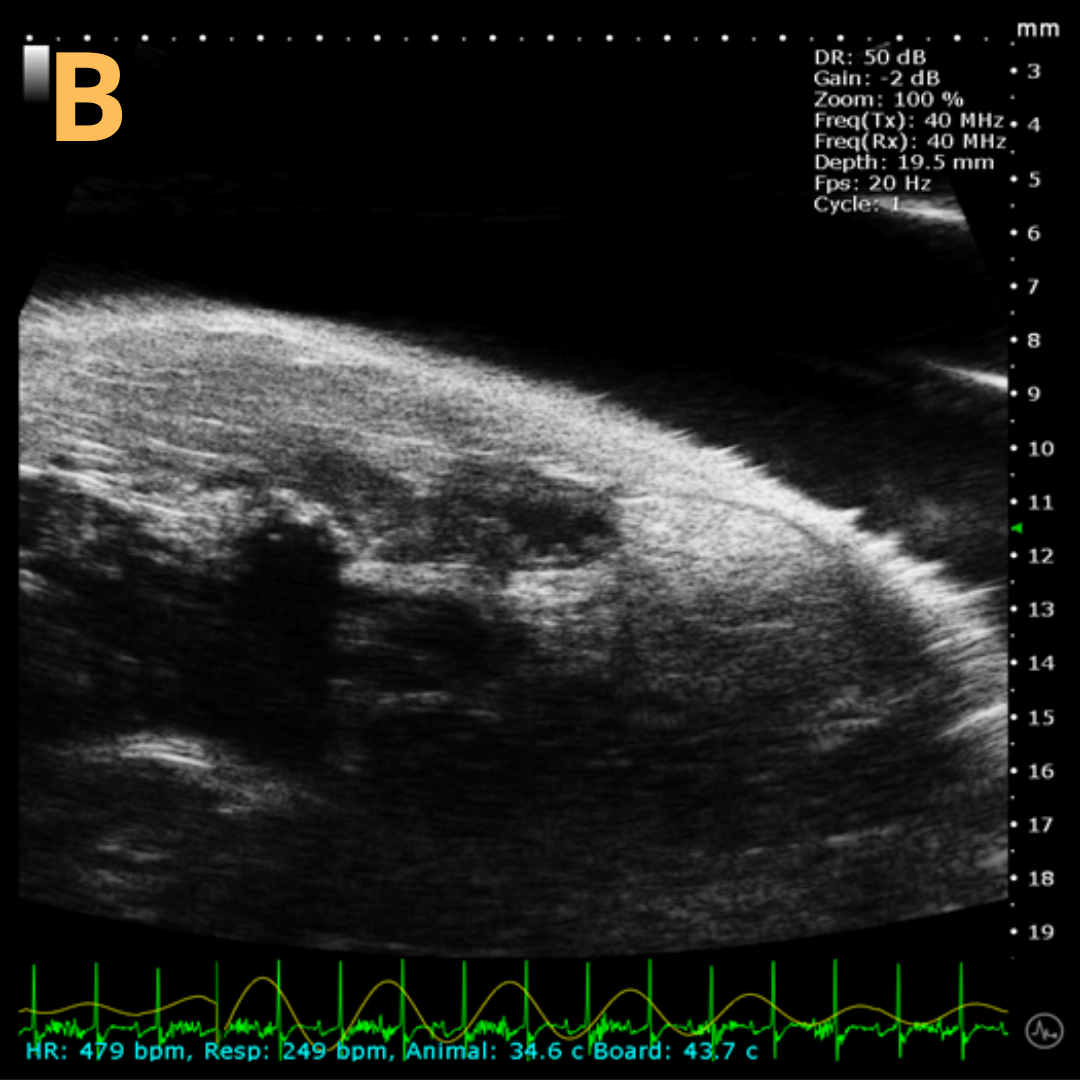

Basic Bladder Imaging

These are imaging from an emptied bladder (A – C) and a full bladder (D – F). This is A) a B-mode video scanning an emptied bladder with B) a still frame with C) the landmarks noted. This is D) a B-mode video scanning a full bladder with E) a still frame with F) the landmarks noted. Imaging on a wildtype C57B6J mouse model – acquired images are from Stephen Zderic’s lab at the Children’s Hospital of Philadelphia.

Ultrasound-Guided Injection

This is A) a B-mode video showing an injection into the bladder with B – D being still frames of B) before injection of any solution with the landmarks noted, C) during injection with bladder becoming notably larger, and D) the end of injection before needle will be removed. Imaging on a wildtype C57B6J mouse model – acquired images are from Stephen Zderic’s lab at the Children’s Hospital of Philadelphia.